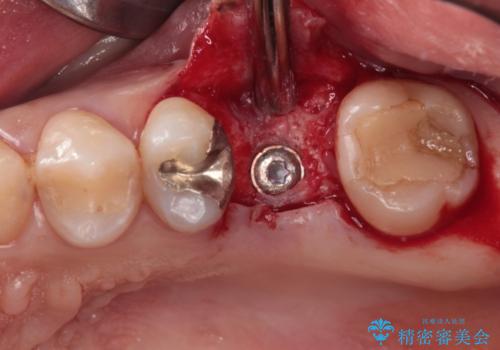

土台の材料を外して顕微鏡下で確認したところ、歯根にまで及ぶ破折が認められたため、インプラント治療を行うこととしました。

他にも銀歯や欠損となっている歯に対しての治療も希望されたため、補綴治療を行うこととしました。